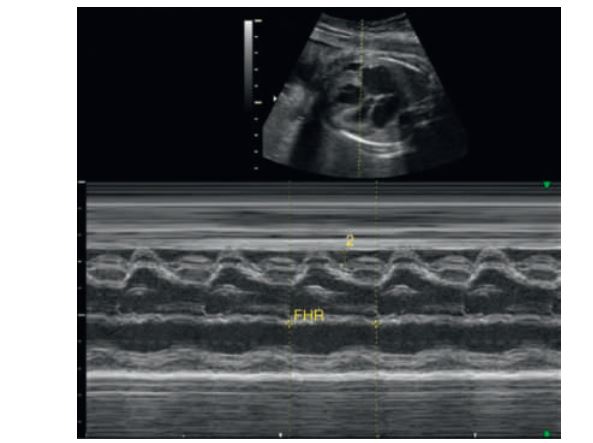

Two-dimensional and M-mode of the ventricular cavities. On the motion mode, time is depicted along the horizontal axis (dots along the top of the image). The distance between two dots represents 1second. Distance is located along the vertical axis. The aorta is shown as the two parallel lines moving as a “unit” through systole (pumping) and diastole (resting).

M-mode measurement of the fetal heart.IVS =

Intraventricular septum

Four-Chamber View: M-Mode